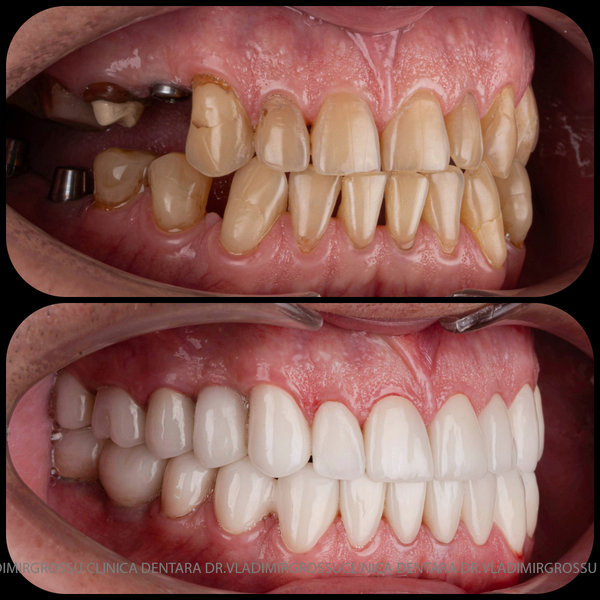

Protezarea pe implanturi dentare este soluția modernă, estetică și funcțională pentru înlocuirea dinților lipsă. Această procedură combină precizia chirurgicală cu tehnologia avansată de laborator pentru a reda pacienților zâmbetul natural, vorbirea clară și capacitatea de a mânca fără restricții.

La Clinica Dentară Dr. Grossu din Chișinău, oferim protezări pe implanturi dentare personalizate, realizate de o echipă multidisciplinară, cu ajutorul celor mai noi tehnologii digitale și materiale biocompatibile.

- Estetică superioară – imită perfect dinții naturali

- Funcționalitate completă – mestecare și vorbire fără restricții